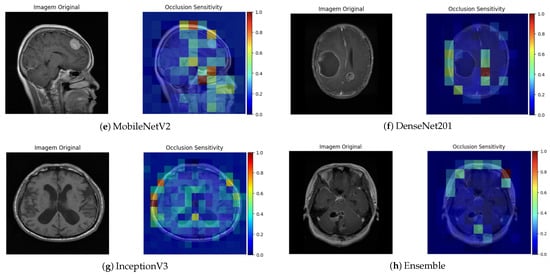

The Occlusion Sensitivity technique complements this analysis by measuring the variation in prediction confidence when different parts of the image are occluded. As shown in the figures associated with this technique (Figure 9), a significant reduction in the probability of classification was observed when the tumor region was partially hidden. This behavior indicates that the model strongly relies on that area for its decision, which supports consistency between the reasoning of the network and the relevant clinical anatomy.

Figure 9.

Occlusion Sensitivity visualization for different architectures.